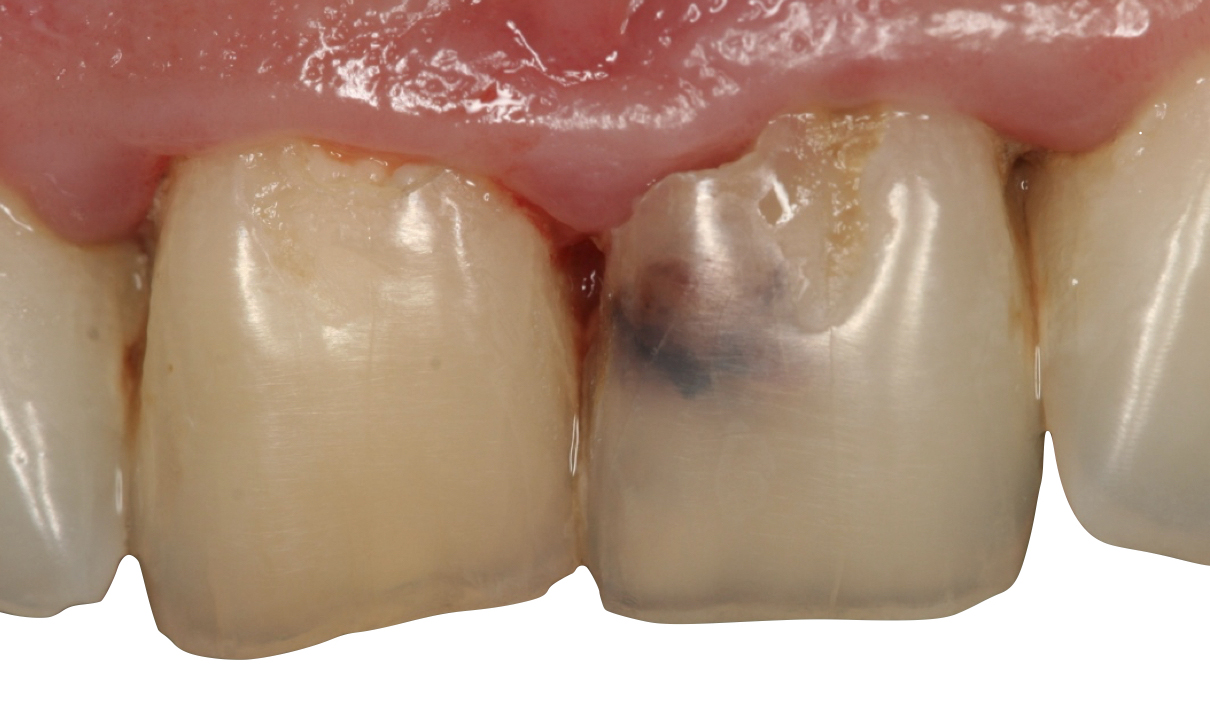

«Il riassorbimento radicolare è una patologia subdola, spesso asintomatica e difficile da diagnosticare, poiché talvolta viene confusa con processi cariosi e, quindi, sottovalutata», prosegue Fornara. Diversi fattori possono danneggiare lo strato predentinale, come i traumi dentari – i più frequenti – l’infiammazione cronica della polpa, le infezioni pulpari subcliniche dovute a processi cariosi o al calore eccessivo durante le fasi di trattamento conservativo/protesico, ma anche stimoli iatrogeni (ortodonzia, sbiancamenti) e procedure pulpari parziali (incappucciamenti, rizotomie in denti vitali eccetera). In generale, i riassorbimenti possono essere causati da traumi, infezioni o trattamenti ortodontici, e, più raramente, da cause sistemiche o idiopatiche».

Tra le sottocategorie ordinate in base all’eziopatogenesi (riassorbimento superficiale esterno, esterno infiammatorio, sostitutivo interno o esterno, ecc.) vi è il riassorbimento cervicale esterno (RCE), che si sviluppa nella zona cervicale del dente, al di sotto dell’attacco epiteliale, spiega Fornara. «Nei casi di diagnosi tardiva, il riassorbimento può raggiungere il terzo medio o apicale della radice, rendendo vano ogni tentativo di trattamento per recuperare il dente. Purtroppo, nelle fasi iniziali è spesso asintomatico, il che ne complica la diagnosi e riduce le possibilità terapeutiche.

Per il paziente, invece, il riassorbimento, proprio perché spesso asintomatico, ha un impatto emotivo rilevante quando accertato. Se si manifesta con sintomi, può comportare dolore, alterazioni estetiche e compromissione funzionale. L’aspetto più difficile da accettare è che un dente apparentemente sano o correttamente trattato possa andare incontro a una distruzione tissutale progressiva e irreversibile oppure richiedere trattamenti complessi o, in ultima istanza, l’estrazione».